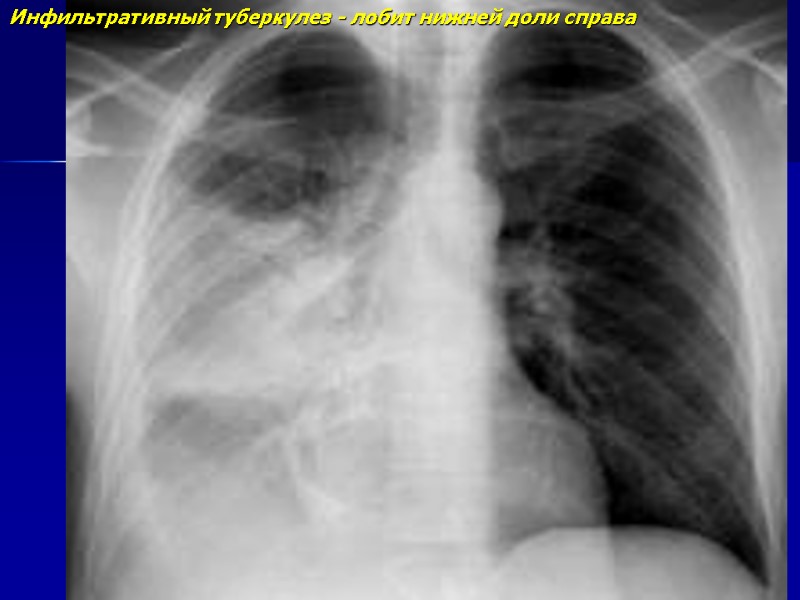

Инфильтративный туберкулез - лобит нижней доли справа